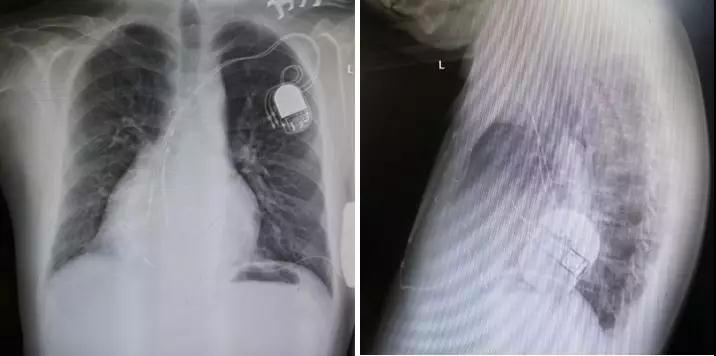

术后影像